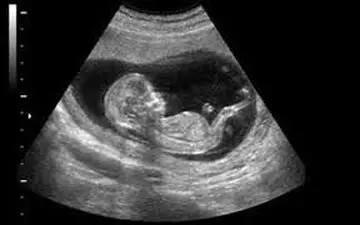

با پیشرفت تکنولوژی در حال حاضر، تعیین جنسیت جنین به روشهای بسیار دقیق و سریعی انجام میشود، با این حال برای تشخیص…